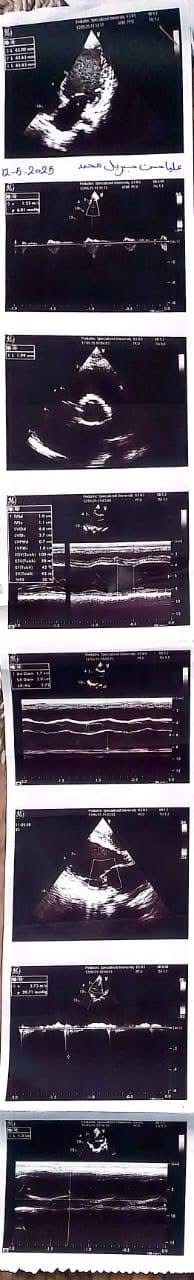

ناشدت أسرة الطفلة عليا حسن، البالغة من العمر أربع سنوات ونصف، الجهات الطبية المعنية وعلى رأسها مؤسسة مجدي يعقوب لأمراض القلب ومستشفى الناس، للتدخل العاجل لإنقاذ حياة ابنتهم، التي تعاني من فشل شديد في عضلة القلب وتضخم كبير بالقلب، ما أدى إلى مضاعفات صحية خطيرة شملت الكبد وأجهزة أخرى من الجسم.

وكشفت أحد أقارب الطفلة تفاصيل الحالة الصحية لها، قائله "عليا حسن بنت خالي 4 سنوات ونصف الأسبوع الماضي جالها استسقاء في معدتها كبير والبنت مكنتش عارفة تتنفس ولا قادرة تتحرك وتعب شديد، لفوا كتير لحد ما عملوا إيكو على القلب وطلع في ضعف شديد في عضلة القلب وتضخم في القلب جامد، ودا طبعا أثر على كل وظائف الجسم وأثر على الكبد بشكل ملحوظ".

وتابعت إحدى أقاربها في منشور لها على الفيسبوك "عليا قعدت في رعاية مستشفى أبو الريش اسبوع، لحد ما كفاءة القلب وصلت ٢٠٪، الحد الأدنى لعمرها ٥٥٪، وخرجت الحمد لله، بس الدكاترة قالوا محتاجة تدخل جراحي سريع لأن حالتها حرجة جدا، محتاجة زرع قلب".